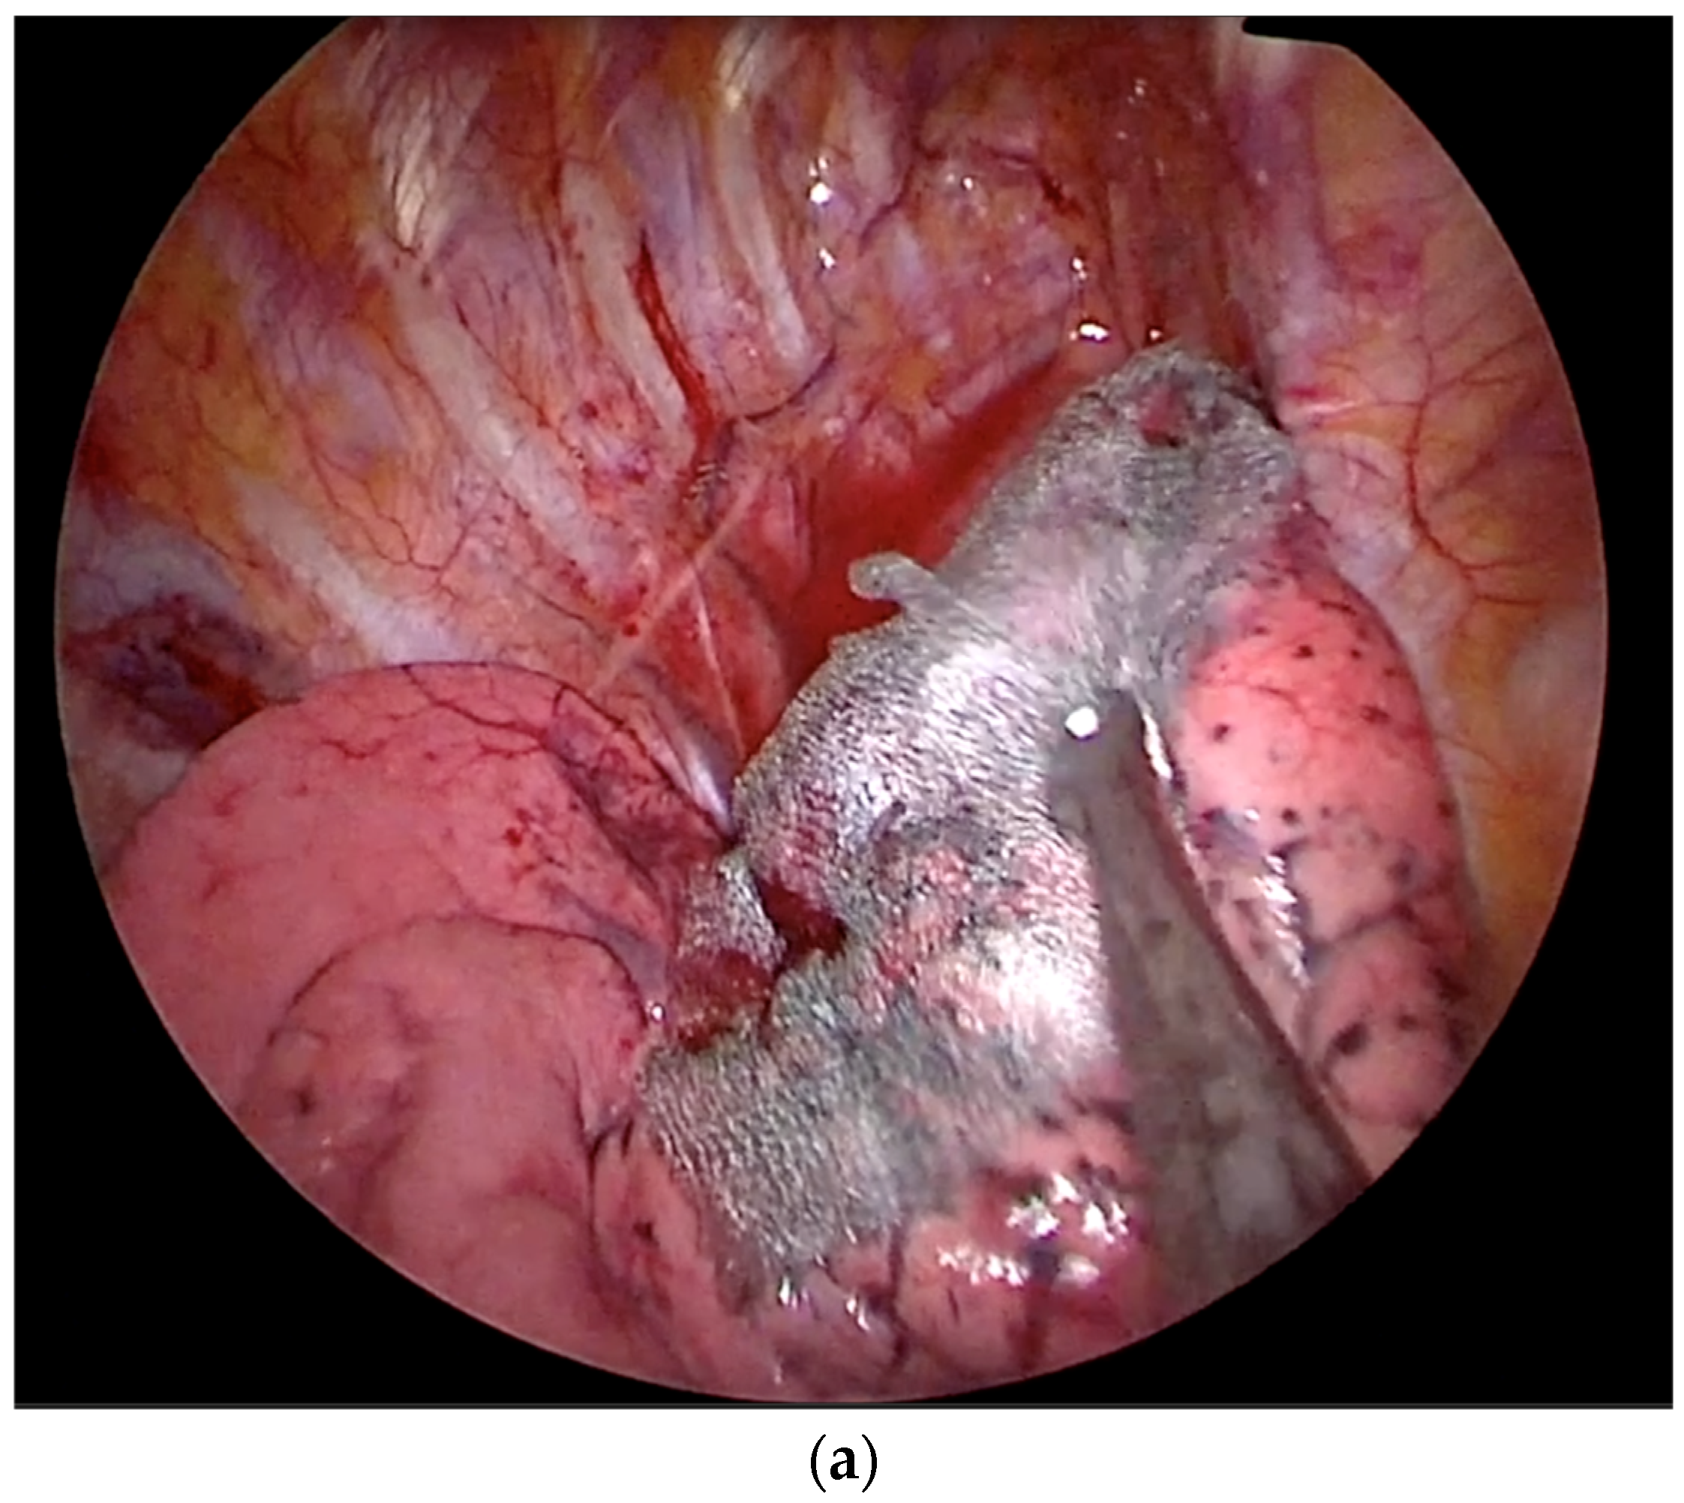

2.2. Technique for Drainless Uniportal VATS Wedge Resection